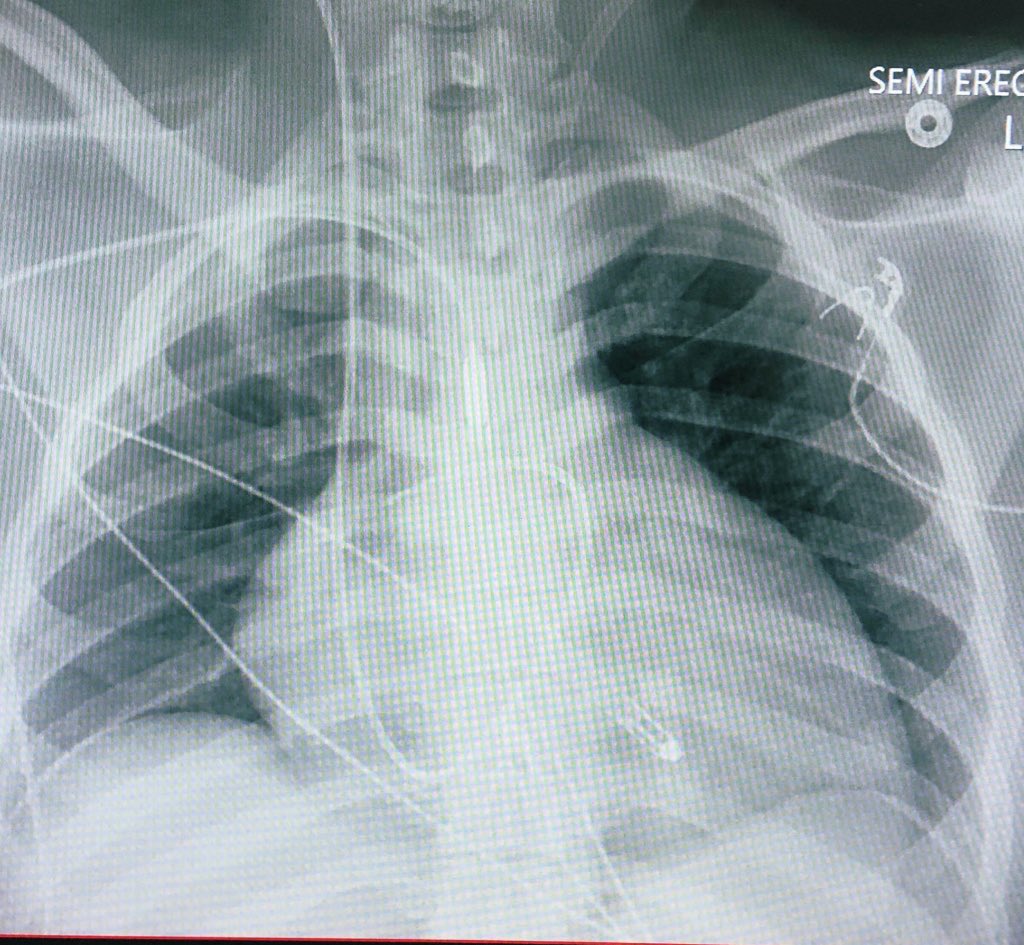

It was a bad month to be a fluid pocket in J31 Ran Lee, MD, FACC Andrew Higgins